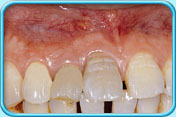

牙齒壞死

因碰撞或蛀牙導致牙齒壞死,壞死的牙髓所釋出的物質滲入象牙質,牙齒就會逐漸呈灰黑色。

治療方法

這類因牙髓壞死而引致的牙齒變色,必須以根管治療(牙髓治療) 處理。

根管治療後